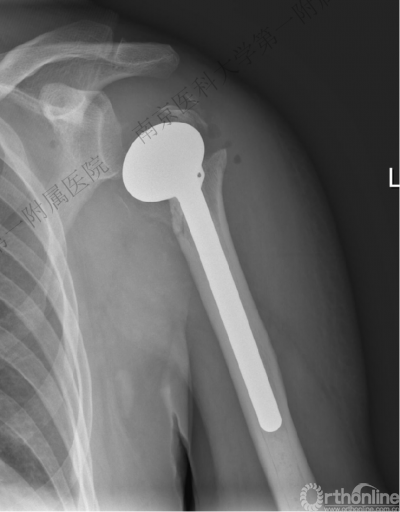

术后肩关节X线正位片

1.当肱骨头缺血坏死风险较大时,可考虑行人工肩关节置换术。

2.人工肩关节置换还适用于肱骨头骨折面积过大、肱骨头软化、陈旧性骨折等。

3.人工半肩置换临床实际应用中仍然存在着一定的问题。